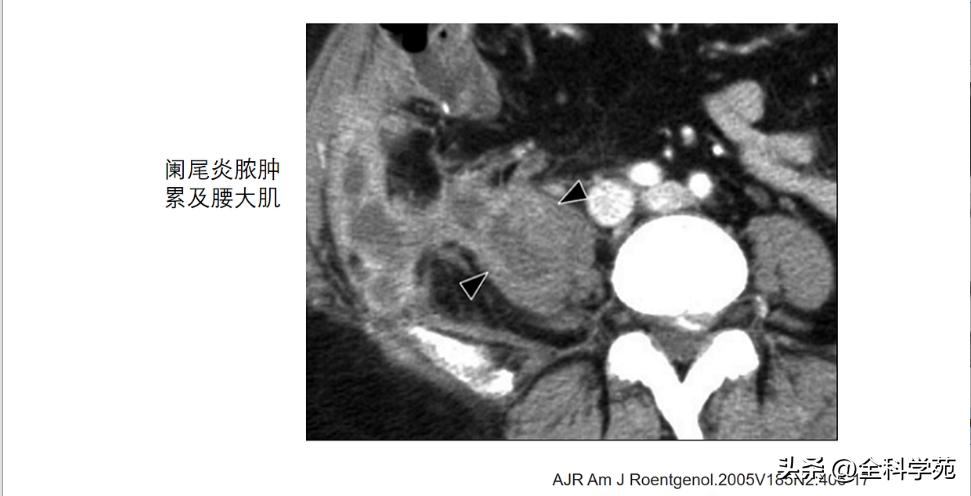

并发症( complications)

◆ 蜂窝织炎和脓肿 (Phlegmon and abscess